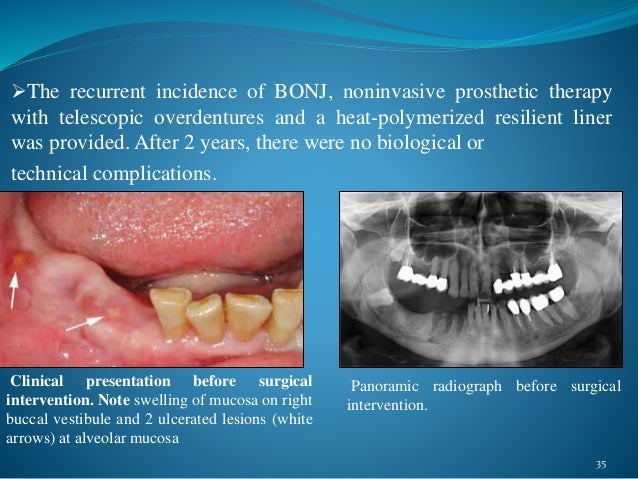

Biocompatibility Of Dental Materials

www.slideshare.net

www.slideshare.net

biocompatibility composite reaction allergic

Clinical Characteristics Of An Allergic Reaction To A Polyether Dental

www.thejpd.org

www.thejpd.org

impression polyether allergic reaction mucosa preoperative

Clinical characteristics of an allergic reaction to a polyether dental. Clinical characteristics of an allergic reaction to a polyether dental. Clinical characteristics of an allergic reaction to a polyether dental